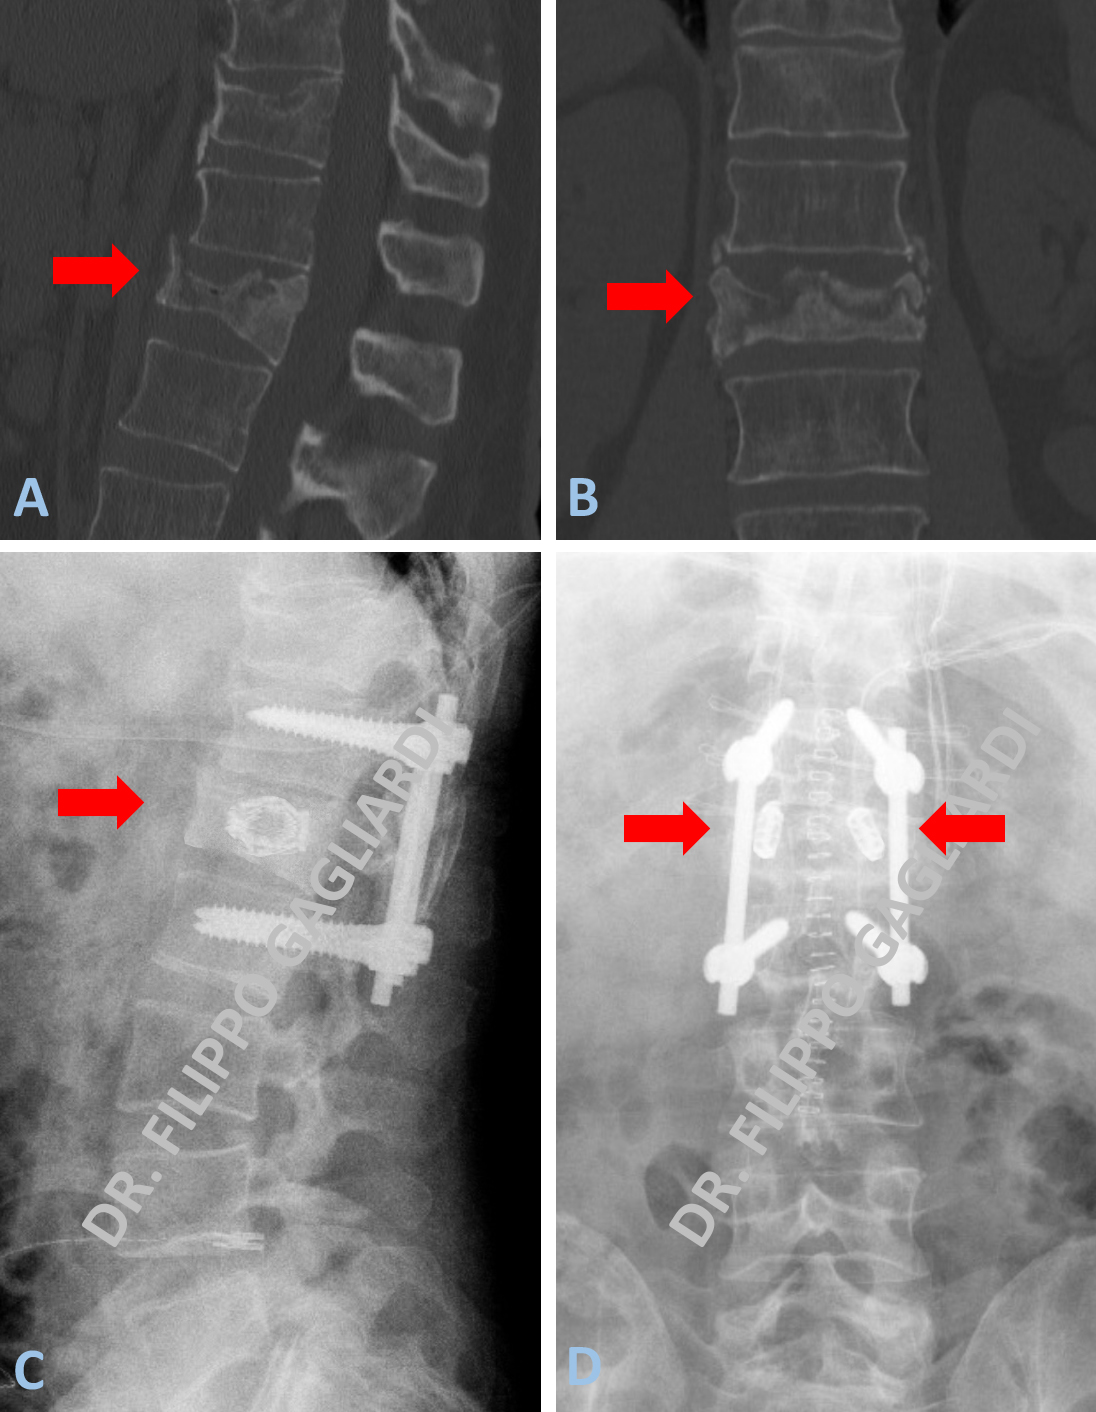

Patologia malformativa spinale Caso di disrafismo spinale condizionante grave instabilità vertebrale. Conseguente scivolamento della quarta vertebra lombare in avanti rispetto alla quinta vertebra lombare (anterolistesi) (freccia azzurra di sinistra, Figura A).

Lo scivolamento è dovuto dall’assenza delle strutture posteriori delle vertebre che ne assicurano la stabilità meccanica. Ad ulteriore complicazione della situazione vi era la presenza di una malformazione delle meningi (membrane che contengono le radici spinali) (meningocele) (freccia azzurra di destra della Figura A). La Paziente si presentava con intenso dolore lombare (lombalgia) e dolore alla gamba destra (sciatalgia). Si procedeva ad intervento di artrodesi (stabilizzazione) vertebrale con riallineamento vertebrale e decompressione delle strutture nervose mediante laminectomia e plastica durale del difetto (mielomeningocele) (freccia rossa della Figura B). Nel post-operatorio si è assistito ad una completa risoluzione della sintomatologia dolorosa della paziente.